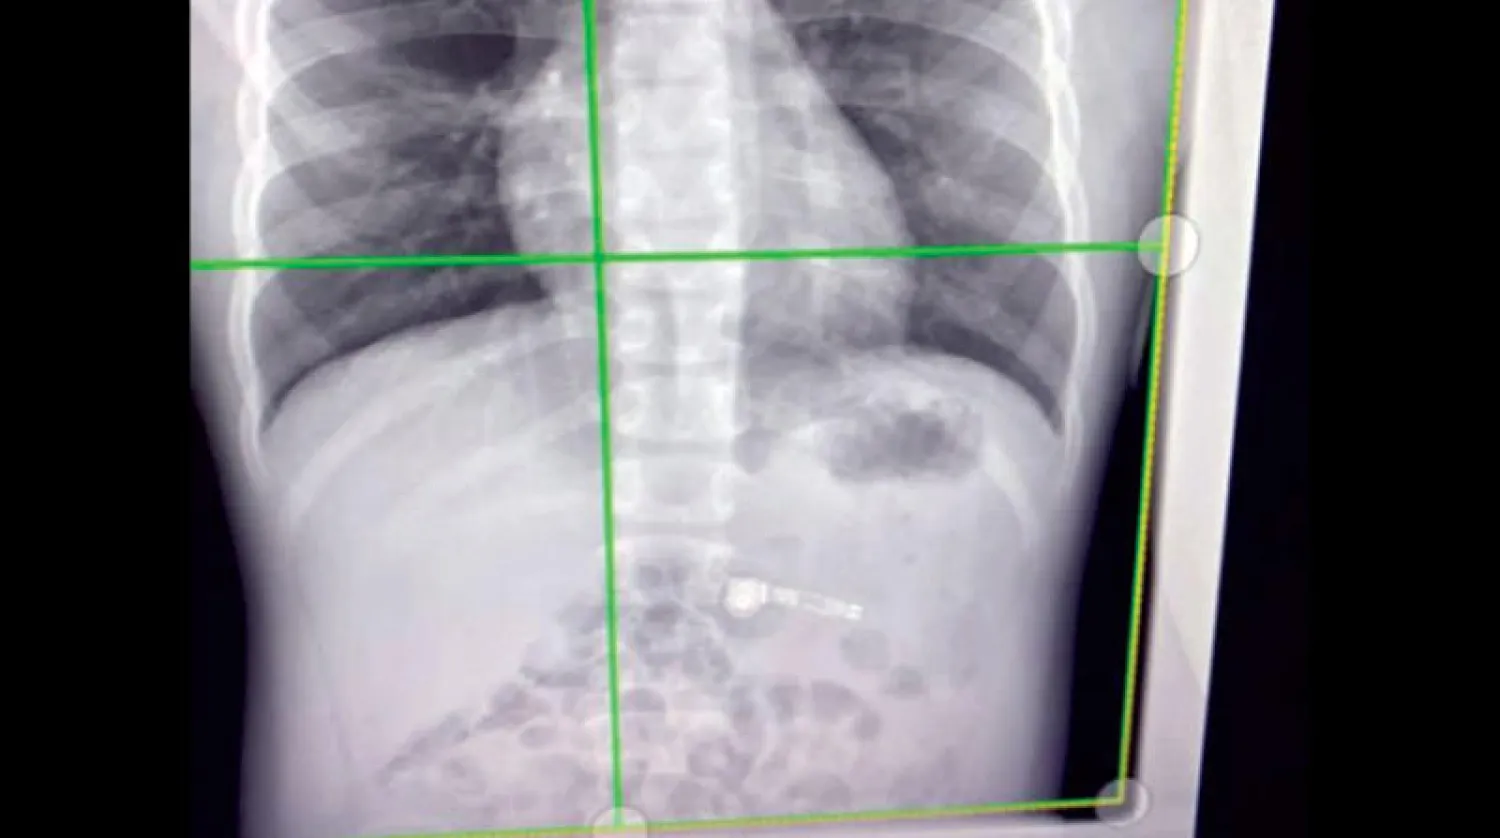

قال براد، المقيم بمنطقة «ووستر» بولاية «ماساتشوستس»، «ذكرت زوجتي ذلك وضحكنا، لكنني شعرت بغصة في حلقي وفكرت أنني ربما ابتلعت شيئاً أثناء نومي. في تلك اللحظة توقفت عن العمل لمدة 10 دقائق للتفكير في الأمر، لكننا قررنا جميعًا أنه سيكون من الأفضل الذهاب إلى المستشفى». وعقب وصوله إلى المستشفى توقع موظفو قسم الاستقبال في البداية أن الطعام الذي تناوله خلال عيد ميلاد زوجته في الليلة السابقة ربما يكون سبب عدم ارتياحه. لكن سرعان ما أثبتت الأشعة السينية خطأ الاعتقاد. أضاف براد، «كان الأمر مضحكًا جدًا. فعندما غادرت الغرفة سمعت ثرثرة في الخارج تقول لا لا يمكن أن يكون كذلك! عادت زوجتي إلي وقالت ملعون أنت لقد ابتلعتها».

اختتم براد، «وقفوا جميعهم في ذهول وقد فتحوا أفواههم وهم ينظرون إلى الأشعة السينية على الشاشة حيث أمكن رؤية السماعة العالقة بوضوح. ولحسن الحظ تمكنوا من التقاطها في النهاية».

الأشعة السينية تظهر السماعة العالقة (غيتي)

الأشعة السينية تظهر السماعة العالقة (غيتي)